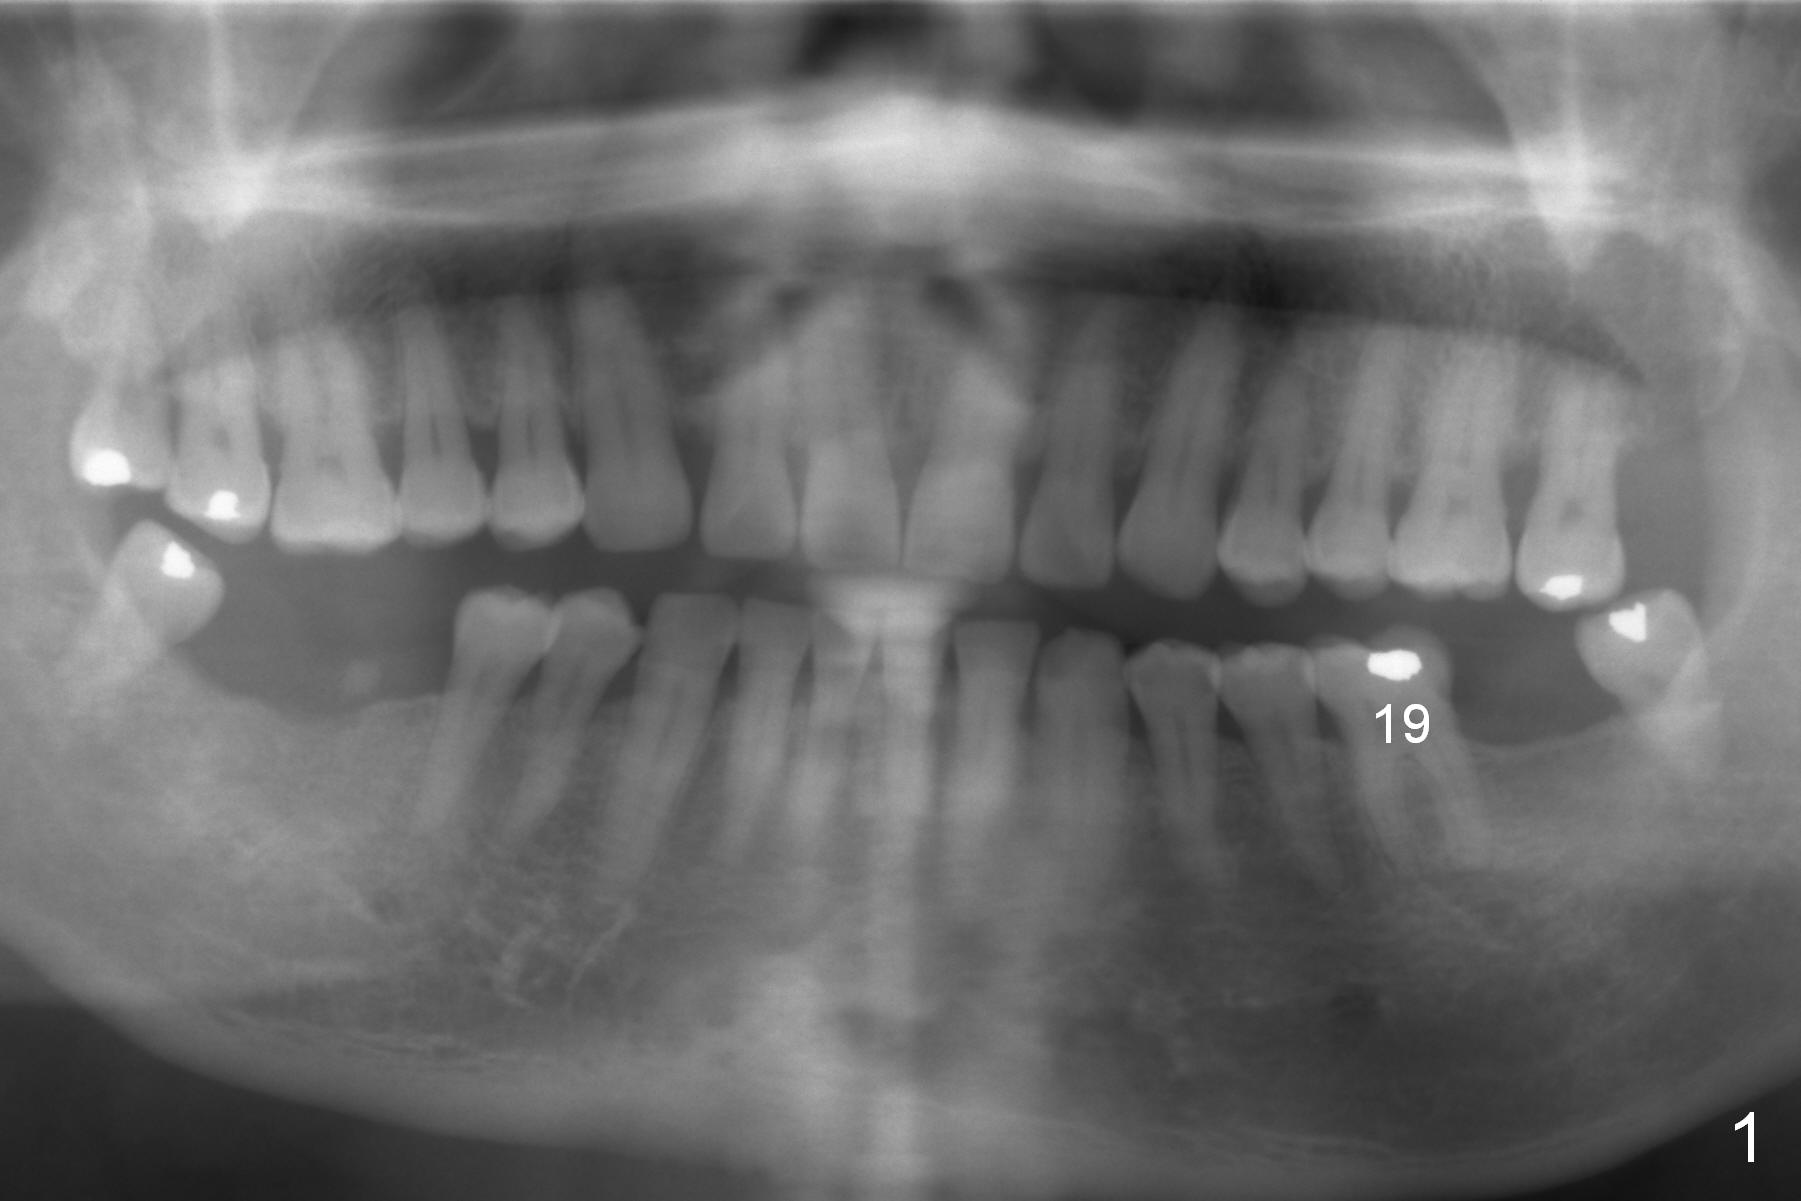

A 59-year-old man has cold sensitivity after chipping the distobuccal cusp of the tooth #19 (Fig.1 (panoramic X-ray taken 5 years ago). He is debating whether to save the tooth or not. If he chooses extraction and implant, the latter can be 18 mm (bone-level (11 (septum, purple in color)+7 (apical, green) mm), Fig.2). If the implant perforates the septum, it will achieve primary stability in the apical bone (the first of 3 fixation points). There is ~5 mm clearance (brown) from the Inferior Alveolar Canal (red dashed line). The cuff of the restorative abutment will be most likely 3 mm (pink), while the abutment is estimated to be 4 mm long (blue). After extraction (Fig.3, no Antibiotic), osteotomy will be initiated through the septum (Fig.4, 6B: red). When an implant is inserted, it may perforate the septum (Fig.5, 6C: green) into the mesial (Fig.6A: M) and distal (D) sockets. The remaining buccal (Fig.6C: B) and lingual (L) septal struts (the rest of two fixation points) contribute to implant stability.